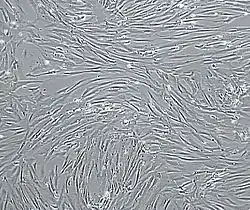

Vascular smooth muscle cells, isolated from human aorta, growing and forming a monolayer in cell culture. | |

Excessive proliferation of vascular smooth muscle cells contributes to the progression of pathological conditions, such as vascular inflammation, plaque formation, atherosclerosis, restenosis, and pulmonary hypertension.[1][2] Recent studies have shown that the majority of cells within atherosclerotic plaque, the predominant cause of heart attack and stroke, are vascular smooth muscle cell derived.[3]